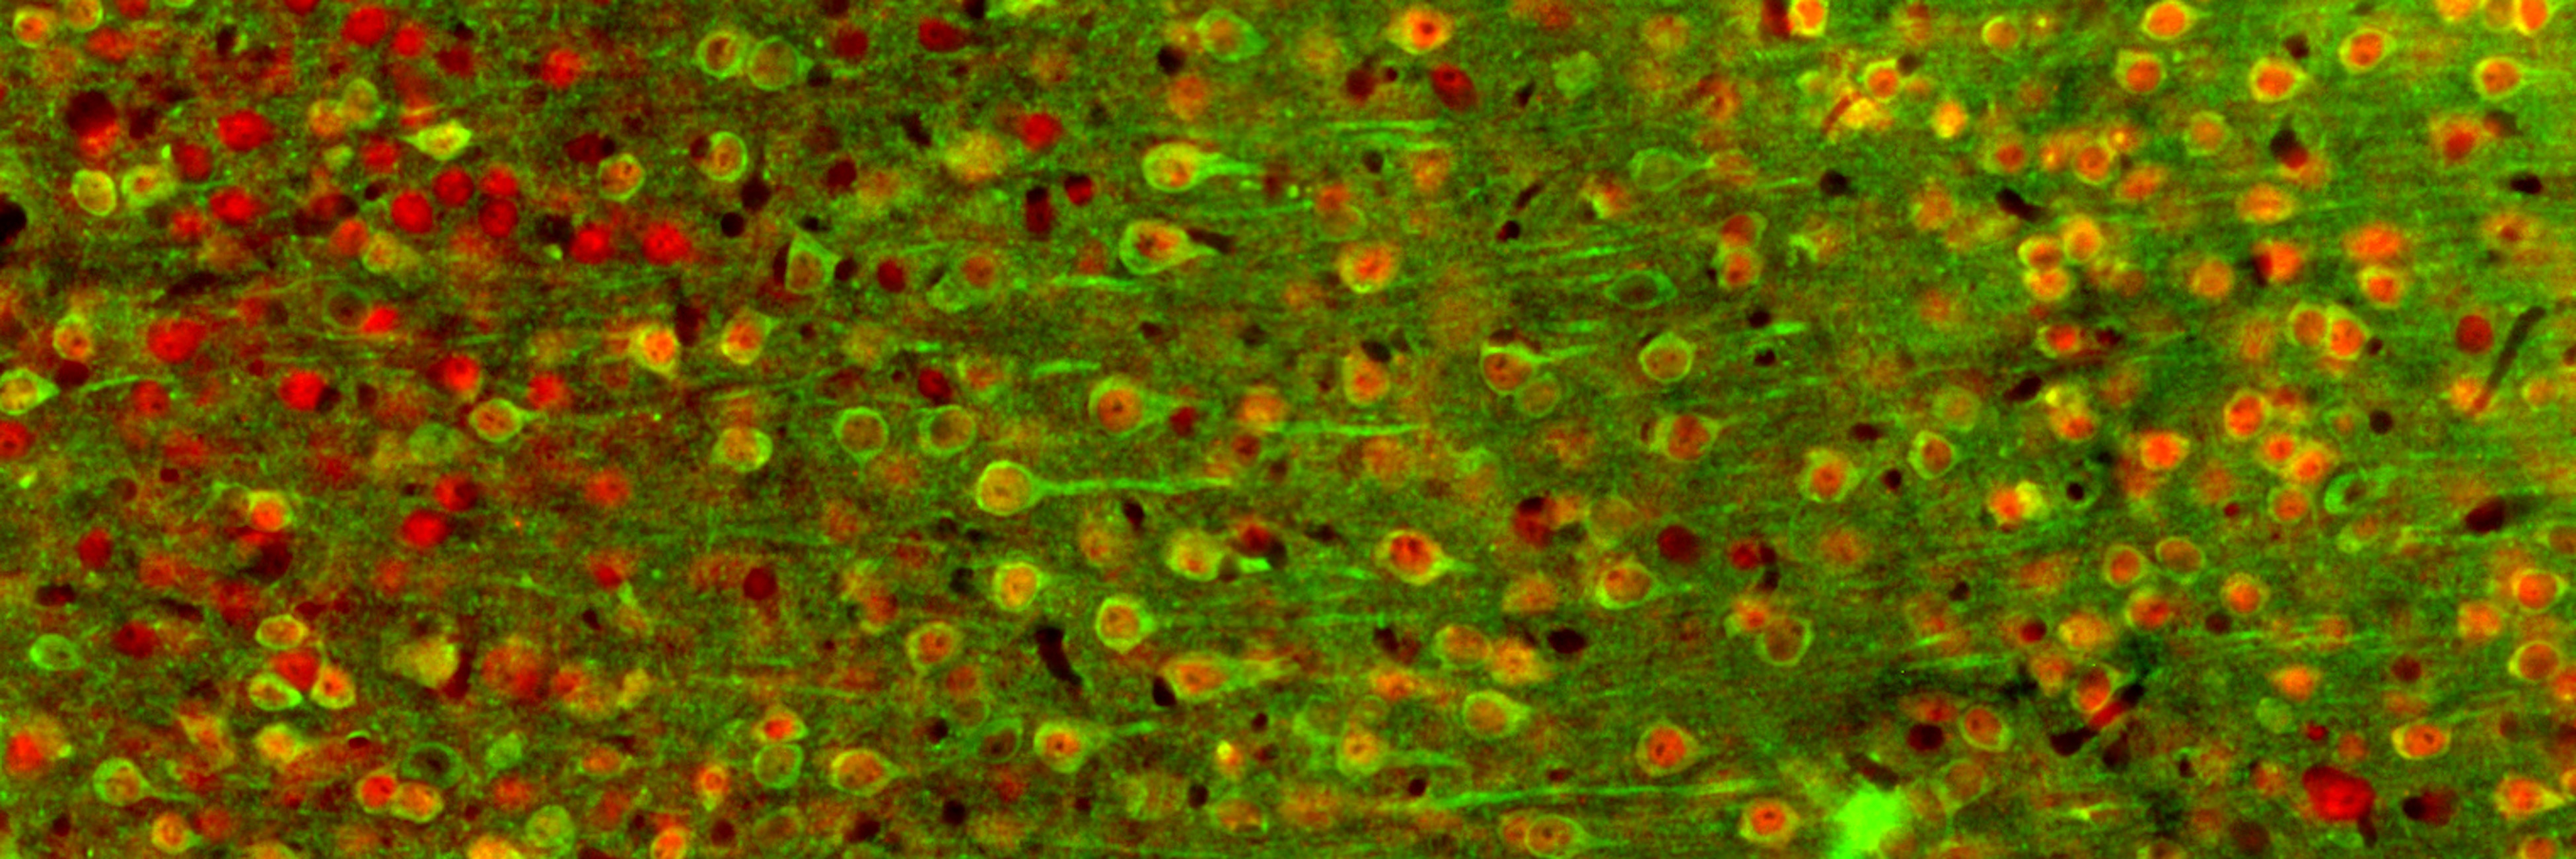

Um sich die Reaktionen der einzelnen Neuronen in der hinteren Inselrinde anzuschauen, nutzte das Team ein Zwei-Photonen-Mikroskop. „Manche der Neuronen antworteten nur auf Kälte, andere nur auf Wärme. Und viele reagierten auf beides“, sagt Vestergaard.